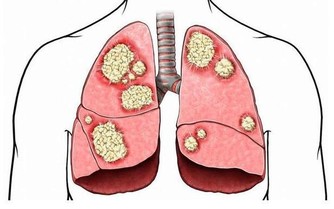

可是,你要當心了,不斷出現腹脹可能是卵巢癌的體徵和症狀之一。

和其他幾乎所有癌症一樣,卵巢癌難以識別,特別是在早期階段。但它終究不是毫無跡象可尋。

一般來說,卵巢癌的症狀包括:

1.排便習慣有變化,包括小便增多、便秘、腹瀉等任何變化;

2.異常陰道出血,特別是絕經後出血,一定要引起警惕;

3.外陰瘙癢或灼痛也是警告標誌;

4.持續消化不良或噁心;

5.性交時疼痛;

6.背部疼痛;

7.感覺一直都很累;

8.原因不明的體重減輕。

9.以及,感覺不斷腹脹;肚子腫脹;肚子或骨盆部位不舒服;吃東西時感覺飽脹或者食慾不振,這都是卵巢癌的症狀。